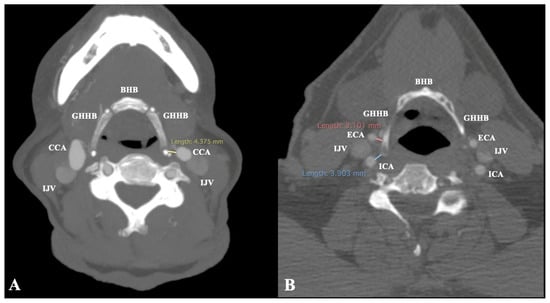

- In cases of suprahyoid CB, the minimum distance GH-CCA was measured (Figure 3)

- In cases of infrahyoid CB, the minimum distances GH-ICA and GH-ECA were measured (Figure 3)